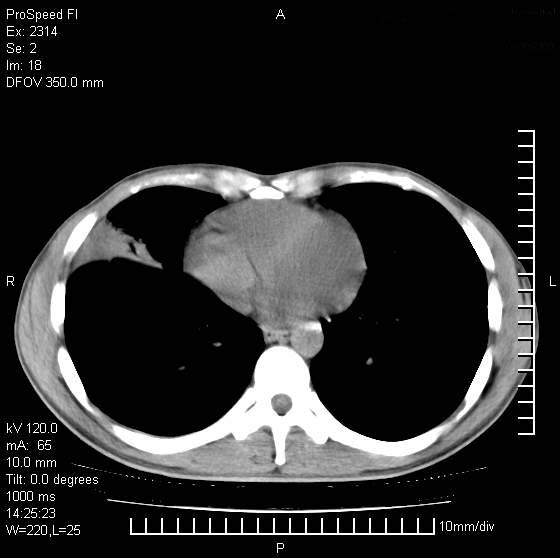

男性,再生障碍性贫血,入院前发热10天,最高40c,右侧胸痛,外院ct示右上,中肺边缘模糊的球性影(就是我现在图中标示的范围),考虑炎症,在我院使用头孢呋辛,洛美沙星10天,高烧消退,自感下午稍有发热,但今天ct示右上,中肺病灶明显扩大,还是考虑炎症,看其中的球型影是否霉菌感染??,是否能排除结核?

肺脓肿,伴双肺播散

支持右肺上叶、中叶外侧段节段性肺炎伴脓肿形成。